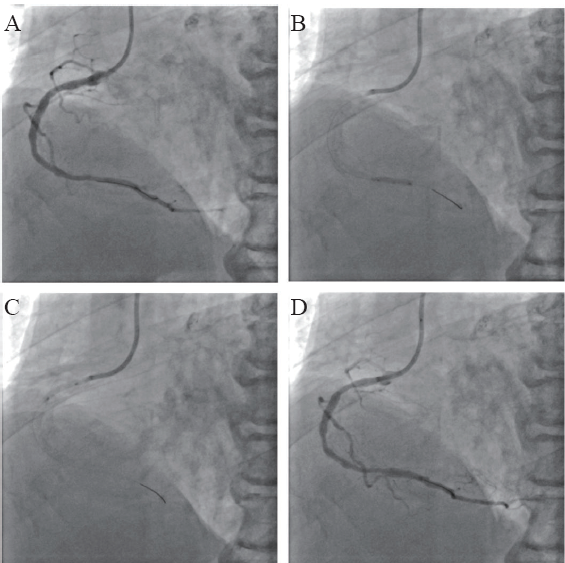

图2 一例NSTEMI患者行右冠状动脉药物球囊扩张术CAG图

A:右冠状动脉药物球囊扩张术前;B、C:药物球囊(3.0 mm×26.0 mm、3.0 mm×26.0 mm、3.5 mm×26.0 mm) 治疗过程;D:药物球囊治疗术后